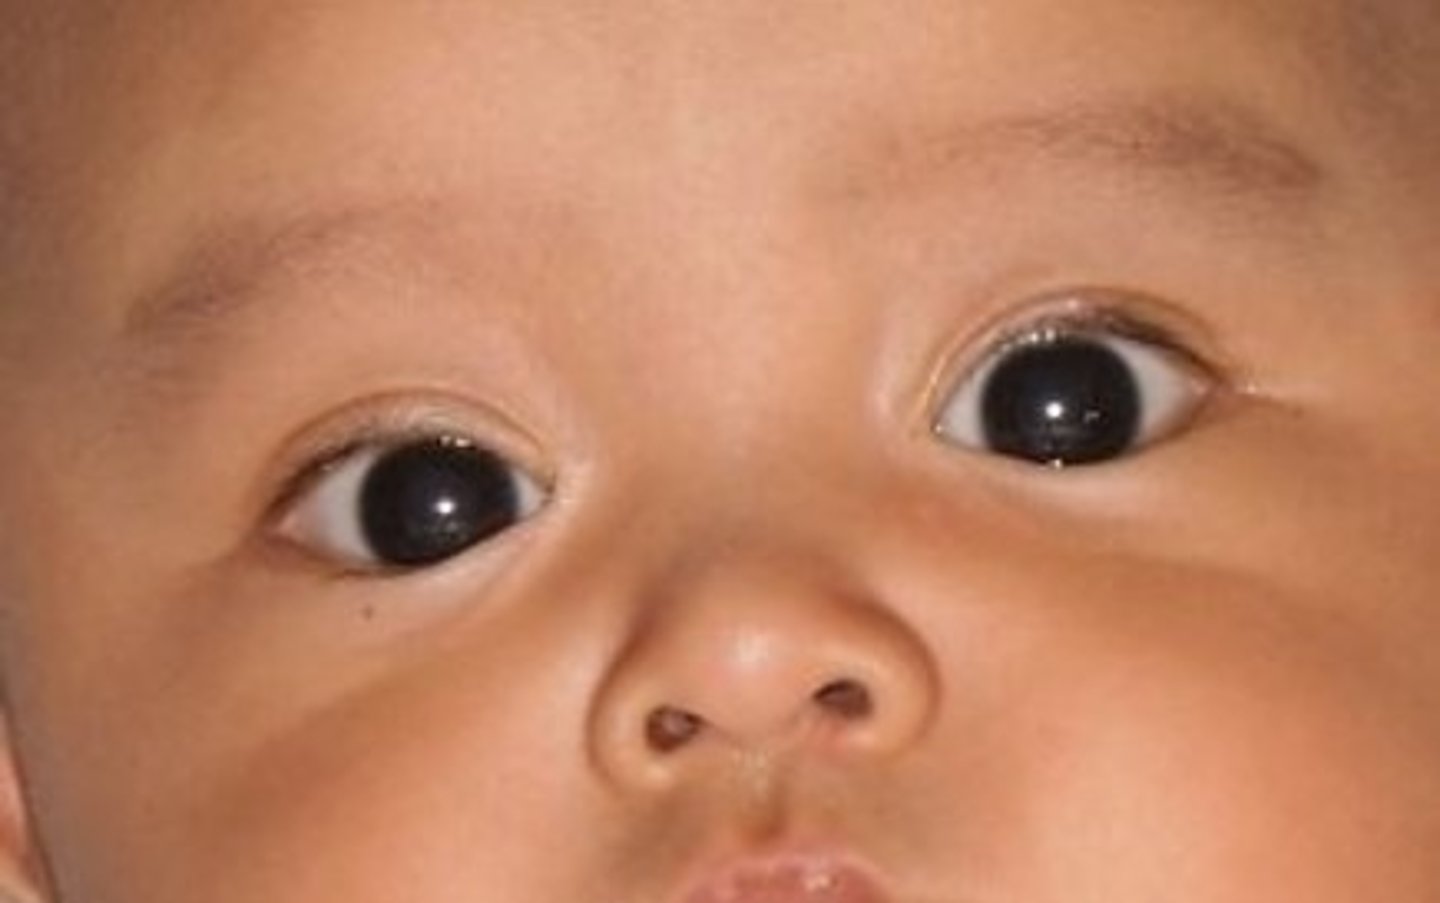

If a child has no red reflex, what diagnosis should you be suspicious of

Retinoblastoma